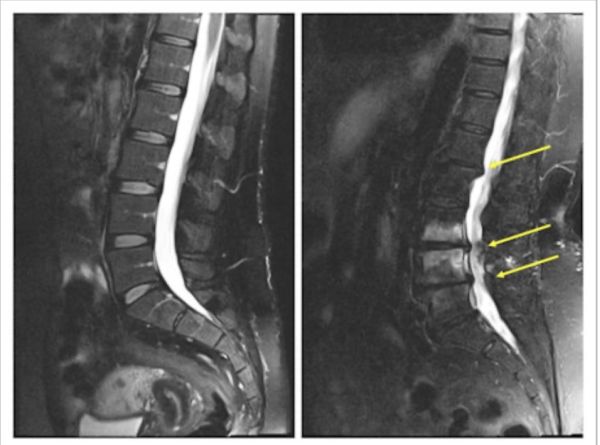

Muayene bulguları içerisinde üzerinde durmamız gereken en önemli unsur radyolojik muayenelerdir. Burada, direkt röntgenler ile beraberinde manyetik rezonans ve bununla beraber gerektiğinde Myelo-MR çekilerek darlıkların nerede ve ne miktarda olduğu tespit edilir.